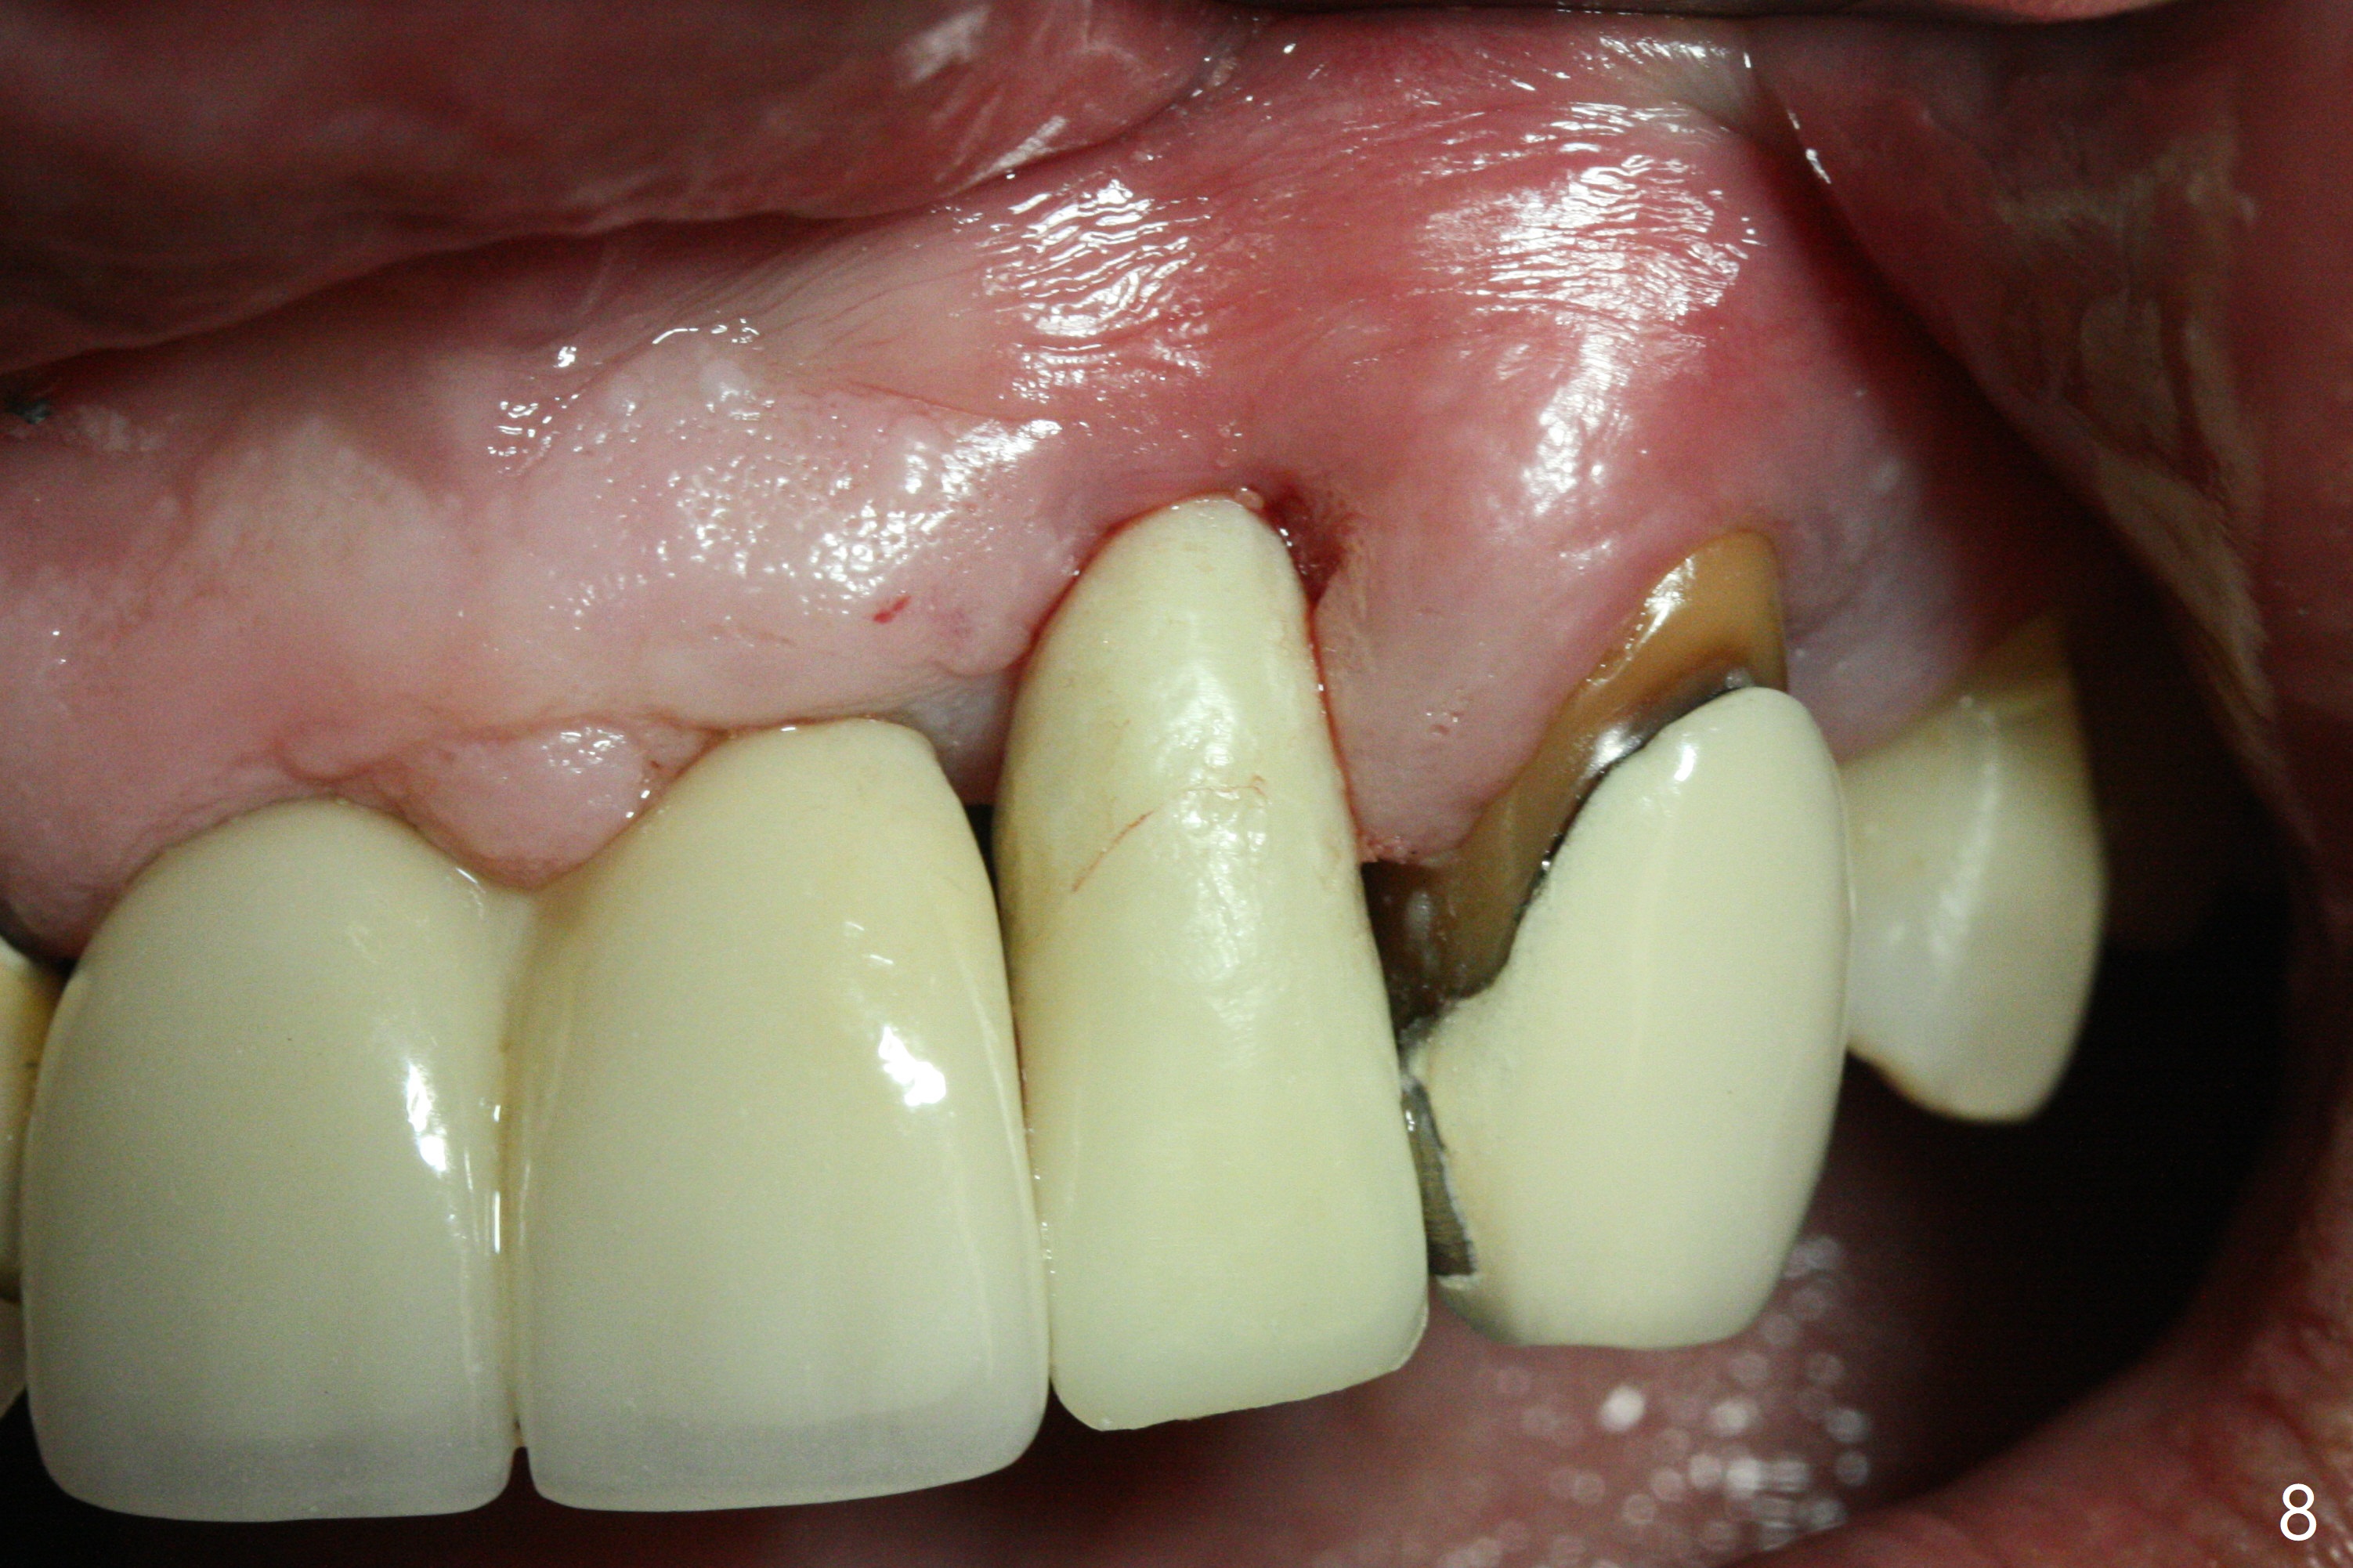

The tooth #10 has severe gingival recession (Fig.1) with loss of the buccal plate (Fig.2 *). After the initial osteotomy depth (Fig.3) increases by 2 mm, a 2.5x14(2) mm 1-piece implant is placed with insertion torque >60 Ncm (Fig.4). Palpation indicates the native bone apparently wider than CT shows. There is no sign of buccal or palatal plate perforation by palpation during osteotomy or implant placement. Vera Graft is placed repeatedly around the coronal threads (Fig.5-7 *). An immediate provisional is fabricated to close the socket (Fig.8). The buccal plate appears to collapse 1 month postop (cortical plate graft apparently more appropriate in this case); the margin of the provisional is trimmed so that the gingiva may grow incisally (Fig.9). The provisional dislodges several times postop due to short abutment. By nearly 4 months postop, the coronal bony defect seems to have been repaired (Fig.10 *). The tooth #11 has tenderness with bone loss (Fig.10 ^), corroborated by CT (distal bone loss, Fig.11 *). Since the apical bone is narrow (Fig.12), a narrow long implant is expected (Fig.13). Use an implant (3.5x13 mm) consistent with those at #14 and 15.